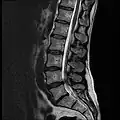

MRI

MRI lumbar spine with degeneration (sagittal T2 FRFSE)

MRI lumbar spine with degeneration (sagittal T1 FSE)

MRI lumbar spine with degeneration (sagittal FAST STIR)- MRI lumbar spine pre-hemilaminectomy (sagittal T2 FRFSE)